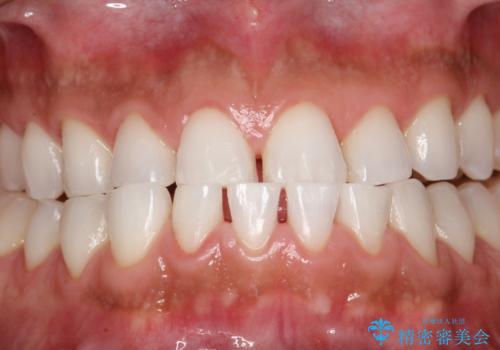

PMTCでお口のメンテナンス

- 痛みや特に気になるところはないが、しっかりとクリーニングしてほしいとのことで来院された患者様です。PMTC 30分コースでのメンテナンスを行いました。

歯を長持ちさせるために、1番の対策が、PMTC を定期的に行うことです。虫歯や歯周病の予防・再発の予防などと、患者様の歯の健康を保つためプロフェッショナルクリーニングを行っています。

痛みや症状が無くても、歯科医院にて専門的なクリーニングを行うことが大切です。